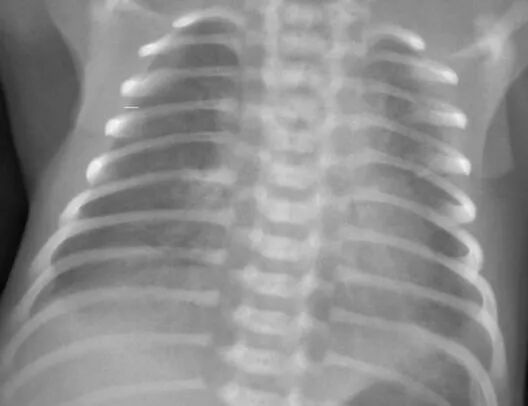

患儿系孕2产2胎龄34+5周,因其母亲“胎盘早剥”在我院产科行剖宫产出生,出生体重2.3kg,出生时羊水清、脐带无绕颈,无产伤及窒息史。出生后出现呻吟样呼吸、气促等表现,经我科会诊,考虑“1、早产低出生体重儿;2、新生儿肺透明膜病?”收新生儿科住院观察治疗。转入我科后予置新生儿辐射治疗台,头罩吸氧改善通气,留置胃管,开放静脉通道等处理,患儿呼吸困难仍呈进行性加重,面色、口唇稍苍白,指端发绀,双肺呼吸音明显减弱,经皮氧饱和度未能达正常范围值,急查胸片可见双肺呈弥漫性磨玻璃状密度增高影,双下肺内带可见少许斑片状密度增高影,提示新生儿肺透明膜病。血气分析提示存在低氧血症,已出现II型呼吸衰竭及呼吸性酸中毒,结合病史、体征及辅助检查,诊断“新生儿肺透明膜病并呼吸衰竭”明确,经与家属充分告知病情后,行鼻塞式CPAP辅助通气(经鼻持续气道正压通气)。

上机后,患儿呻吟样呼吸消失,气促减轻,肤色转红润,指端无发绀,经相关对症及支持治疗,逐渐调整呼吸机参数,3天后顺利撤机,复查胸片及血气分析等结果均明显好转。后续经预防感染、预防出血、静脉营养支持等治疗后,第10天顺利出院。